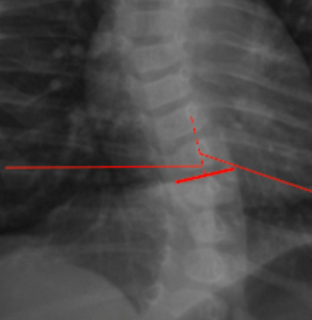

Rib-Vertebra Angle Difference (RVAD)

X-Ray